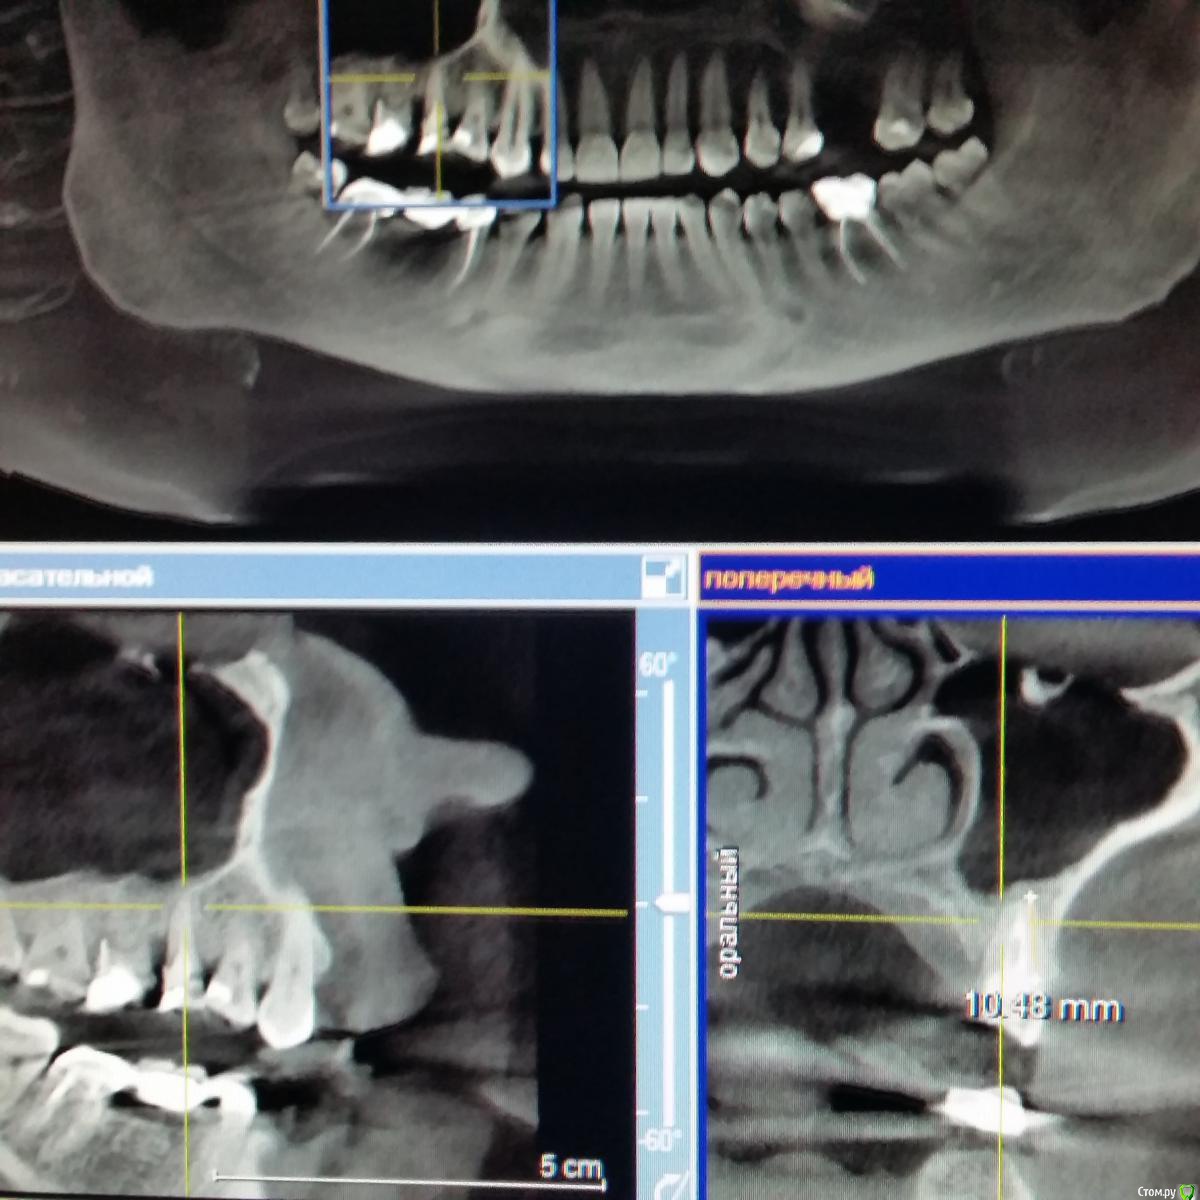

inycik Опубликовано 12 декабря, 2016 Поделиться Опубликовано 12 декабря, 2016 Уважаемые специалисты, помогите советом. Мнения врачей расходятся. Все зубы перелечила. это кт до лечения. Сейчас под временными коронками. Предлагают имплантацию 1.5,2.5 и 4.5 (убрать мост, т.к. 4.6 сильно разрушен). 1.5 удалить и сразу же имплантВопросы. 1. У меня грудной ребенок. Можно ли делать имплантацию2. Нужен ли синус-лифтинг3. Обнаружили проблему в пазухе, что это и может ли повлиять на имплантацию4. Может лучше подождать, чтобы зажило после удаления зубаСсылка на кт https://drive.google.com/file/d/0B7fYoL1llb1HQnEyM0FmOVFxVEU/view?usp=sharing Ссылка на комментарий

Nazim_NV86 Опубликовано 15 декабря, 2016 Поделиться Опубликовано 15 декабря, 2016 Вы выложили 2.5В такой ситуации можно установить 8-9мм имплантат с закрытым лифтом. Антибиотикотерапия желательна. Ссылка на комментарий

Bier Опубликовано 15 декабря, 2016 Поделиться Опубликовано 15 декабря, 2016 с 16м тоже проблема. Скорее всего надо удалять и 15 и 16 и ждать 3-4 мес, потом имплантироваться. Надо еще покрутить КТ, но карман между 16 и 15 очень уж большой.25 с закрытым синуслифтингом, антибиотики не нужны. Ссылка на комментарий